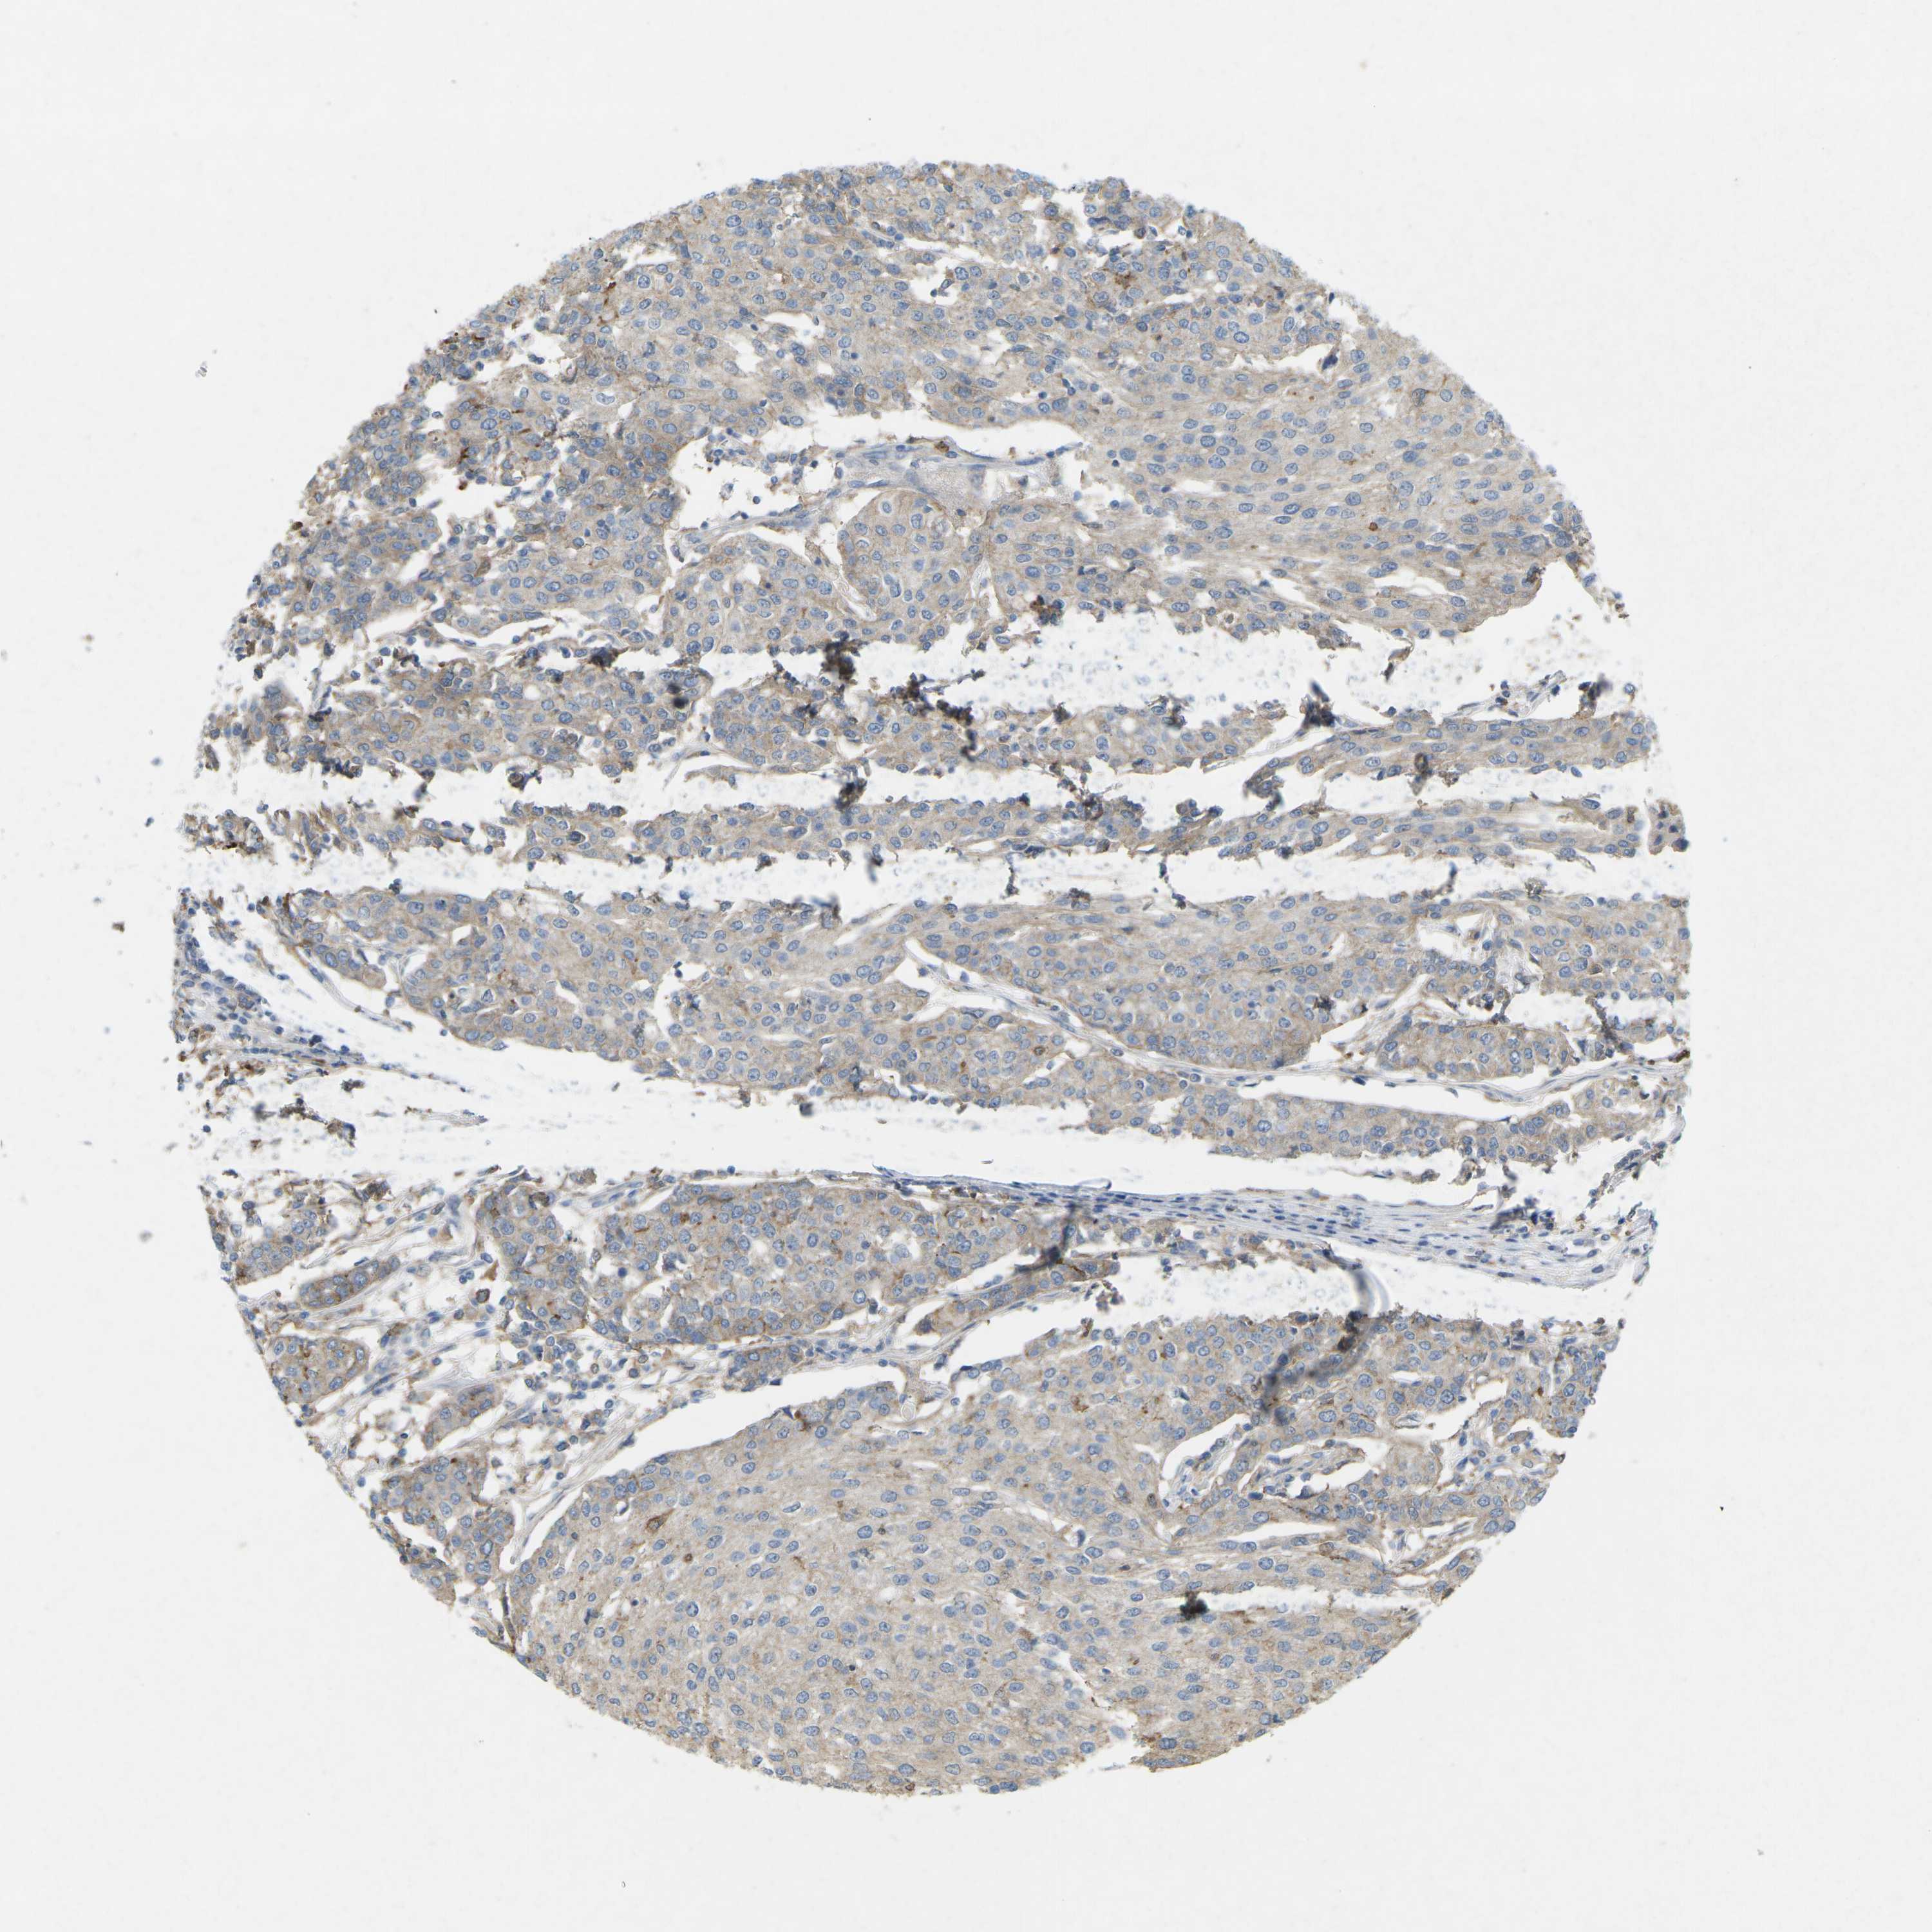

UROTHELIAL CANCER - Protein expressioni

A mouse-over function shows sample information and annotation data. Click on an image to view it in a full screen mode. Samples can be filtered based on level of antibody staining by selecting one or several of the following categories: high, medium, low and not detected. The assay and annotation is described here.

Note that samples used for immunohistochemistry by the Human Protein Atlas do not correspond to samples in the TCGA dataset.

Antibody stainingi

Antibody staining in the annotated cell types in the current human tissue is reported as not detected, low, medium, or high, based on conventional immunohistochemistry profiling in selected tissues. This score is based on the combination of the staining intensity and fraction of stained cells.

Each image is clickable and will lead to virtual microscopy that enables deeper exploration of all samples and also displays staining intensity scores, fraction scores and subcellular localization as well as patient and tissue information for each sample.

Antibody HPA017254

Antibody CAB016231

Antibody CAB022105

Staining

High

Medium

Low

Not detected

Intensity

Strong

Moderate

Weak

Negative

Quantity

>75%

75%-25%

<25%

None

Location

Nuclear

Cytoplasmic/membranous

Cytoplasmic/membranous,nuclear

Urothelial carcinoma, Low grade

Urothelial carcinoma, High grade